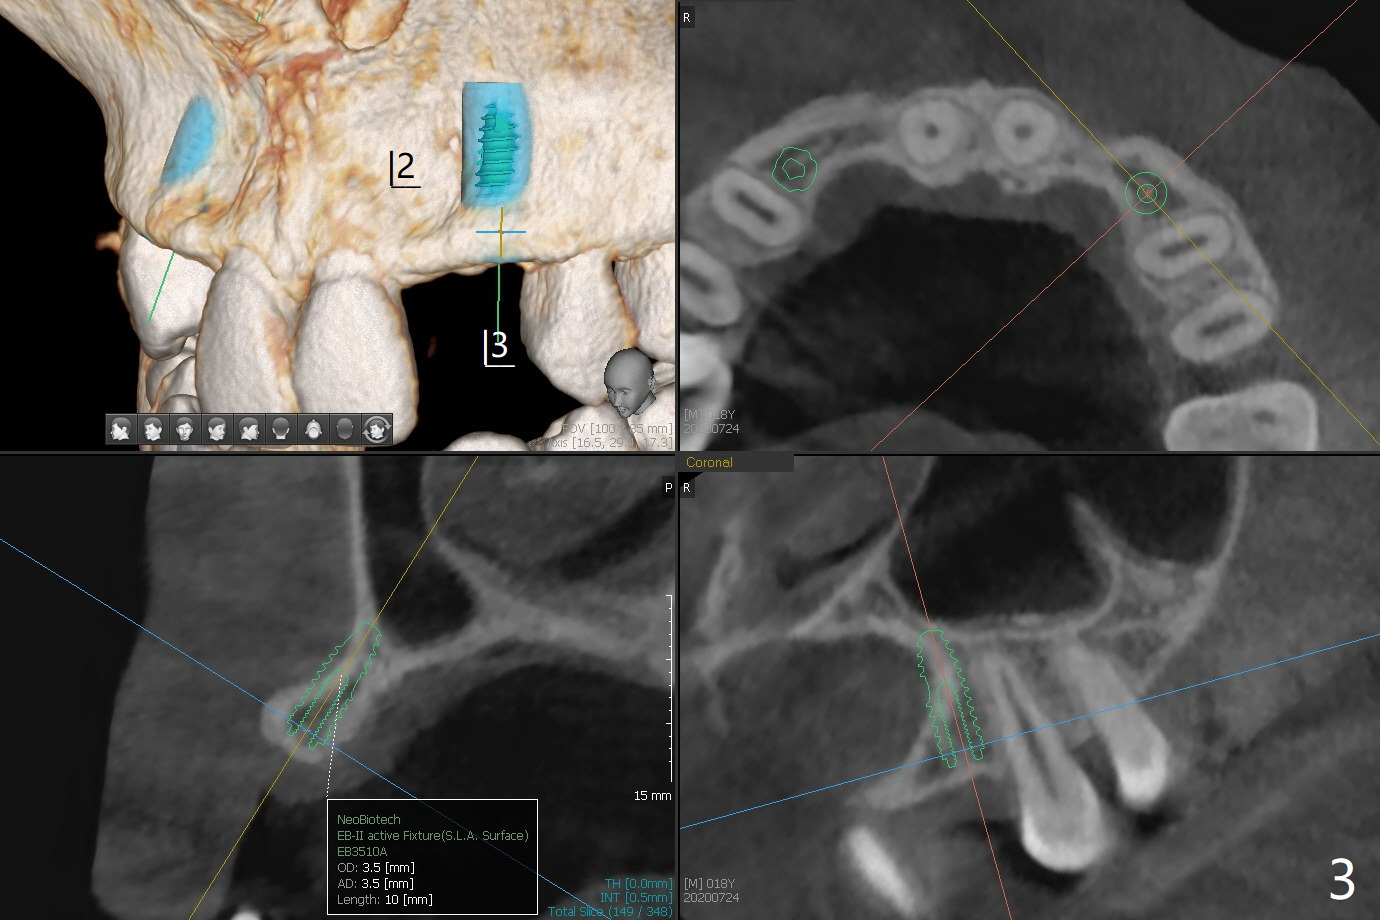

18岁男先天缺失上颌2,3(图一:双侧),2严重颊侧骨壁凹陷(图二,三:2),准备在两侧3种植(图二,三:绿色),做悬臂桥,右上植体3.5乘10毫米,但是必须用带有角度基台修复。而左上3用同样大小植体,颊侧螺纹暴露(图三 B),你会怎么处理?一个月病人到外州上学,而且治疗必须在十九岁前完成,保险可多付钱。为了能在颊侧植骨(图四红圆圈),在左上1近中做一个垂直切口(图五,六红实线),潜行分离骨膜直到4近中(红虚线),并且放置骨块,让骨膜离开颊侧骨板,钻洞时不损伤骨膜。植体放入后,检查颊侧骨块是否足够,最后放置PRF膜,缝合。